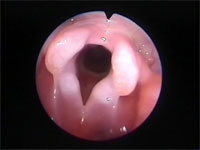

Abb 2 Larynx-schwer-einsehbar

Abbildung 2: Blick in den Pharynx der Katze. Der Kehlkopf ist nur schwer einzusehen.

Katzen sind wegen der Kleinheit ihres Oropharynx nicht immer leicht zu intubieren. Durch die Wölbung der Zungenoberfläche ist die relativ tief liegende Epiglottis nicht immer direkt einsehbar.